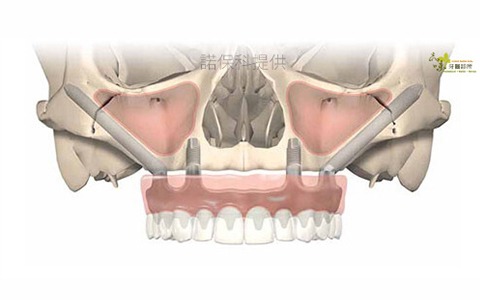

Zygoma 顴骨植體介紹

上顎骨萎縮(Maxillary atrophy)指的是骨頭消失,鼻竇氣室過大,齒槽骨嚴重萎縮甚至跟蛋殼一樣薄。有些人牙齒拔除前已經有發炎感染,拔完後甚至連骨頭都不存在。

顴骨植體手術技術是口腔重建最困難的手術之一,可以處理許多鼻竇補骨感染,植牙失敗造成齒槽骨流失的問題,建議由有經驗受過訓練的專業醫師執行。

品味牙醫使用 All-on-4 搭配顴骨植體全口重建作法,將顴骨植體卡在顴骨(Zygoma bone)最堅硬地方,當天可以裝上牙齒,平均分散咬合受力。